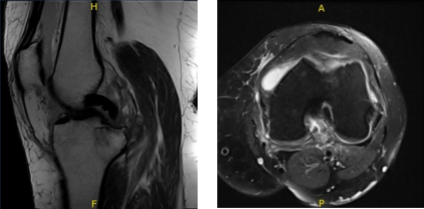

An MRI result was presented during her follow-up visit and it showed Osteoarthrosis with high-grade cartilage loss in the medial compartment and high-grade cartilage loss central trochlear cartilage with low-grade chondral loss patellar cartilage.

Subchondral cystic changes and edema in the medial tibia are seen. This may be secondary to osteoarthritis although I cannot exclude developing insufficiency fracture medial tibia.

Large radial tear posterior horn medial meniscus which is peripherally extruded. Pes anserine bursitis. Large knee joint effusion with loose intra-articular body.

MRI-Left Knee Non-contrast